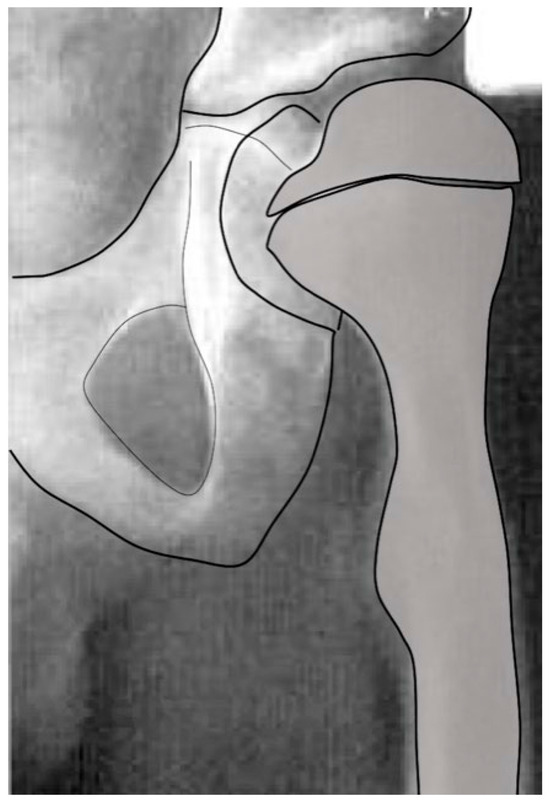

3.2.1. Normal Development

3.2.2. Biomechanical Principles Driving Femoral Shape Development

3.3. Abnormal Hip Development in Children with CP and CP-like Conditions